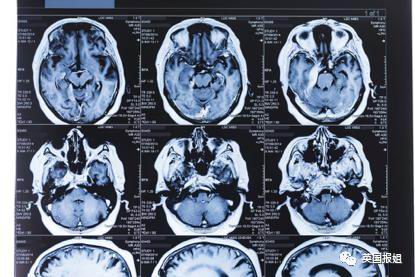

而.ICU.谵妄症之所以在新冠患者中尤其常见,主要是因为他们有着共同的生存环境:大脑缺氧和使用镇静剂。

进入.ICU.的重症新冠肺炎患者,本身存在低氧的症状,因此需要长时间的使用呼吸机。也就意味着他们需要更长的时间、剂量更大的镇静剂。完美契合了.ICU.谵妄症的发生条件。

也是因为这个,有人说,新冠病毒的大流行简直就是谵妄症的工厂。

旧金山加利福尼亚大学神经病学系主任.Andrew.Josephson.表示,虽然新冠病毒和.ICU.谵妄症之间的关系还不能就此定论,但可以确定的是,新冠肺炎导致的精神病学问题,比其他身体上的后遗症更加普遍。